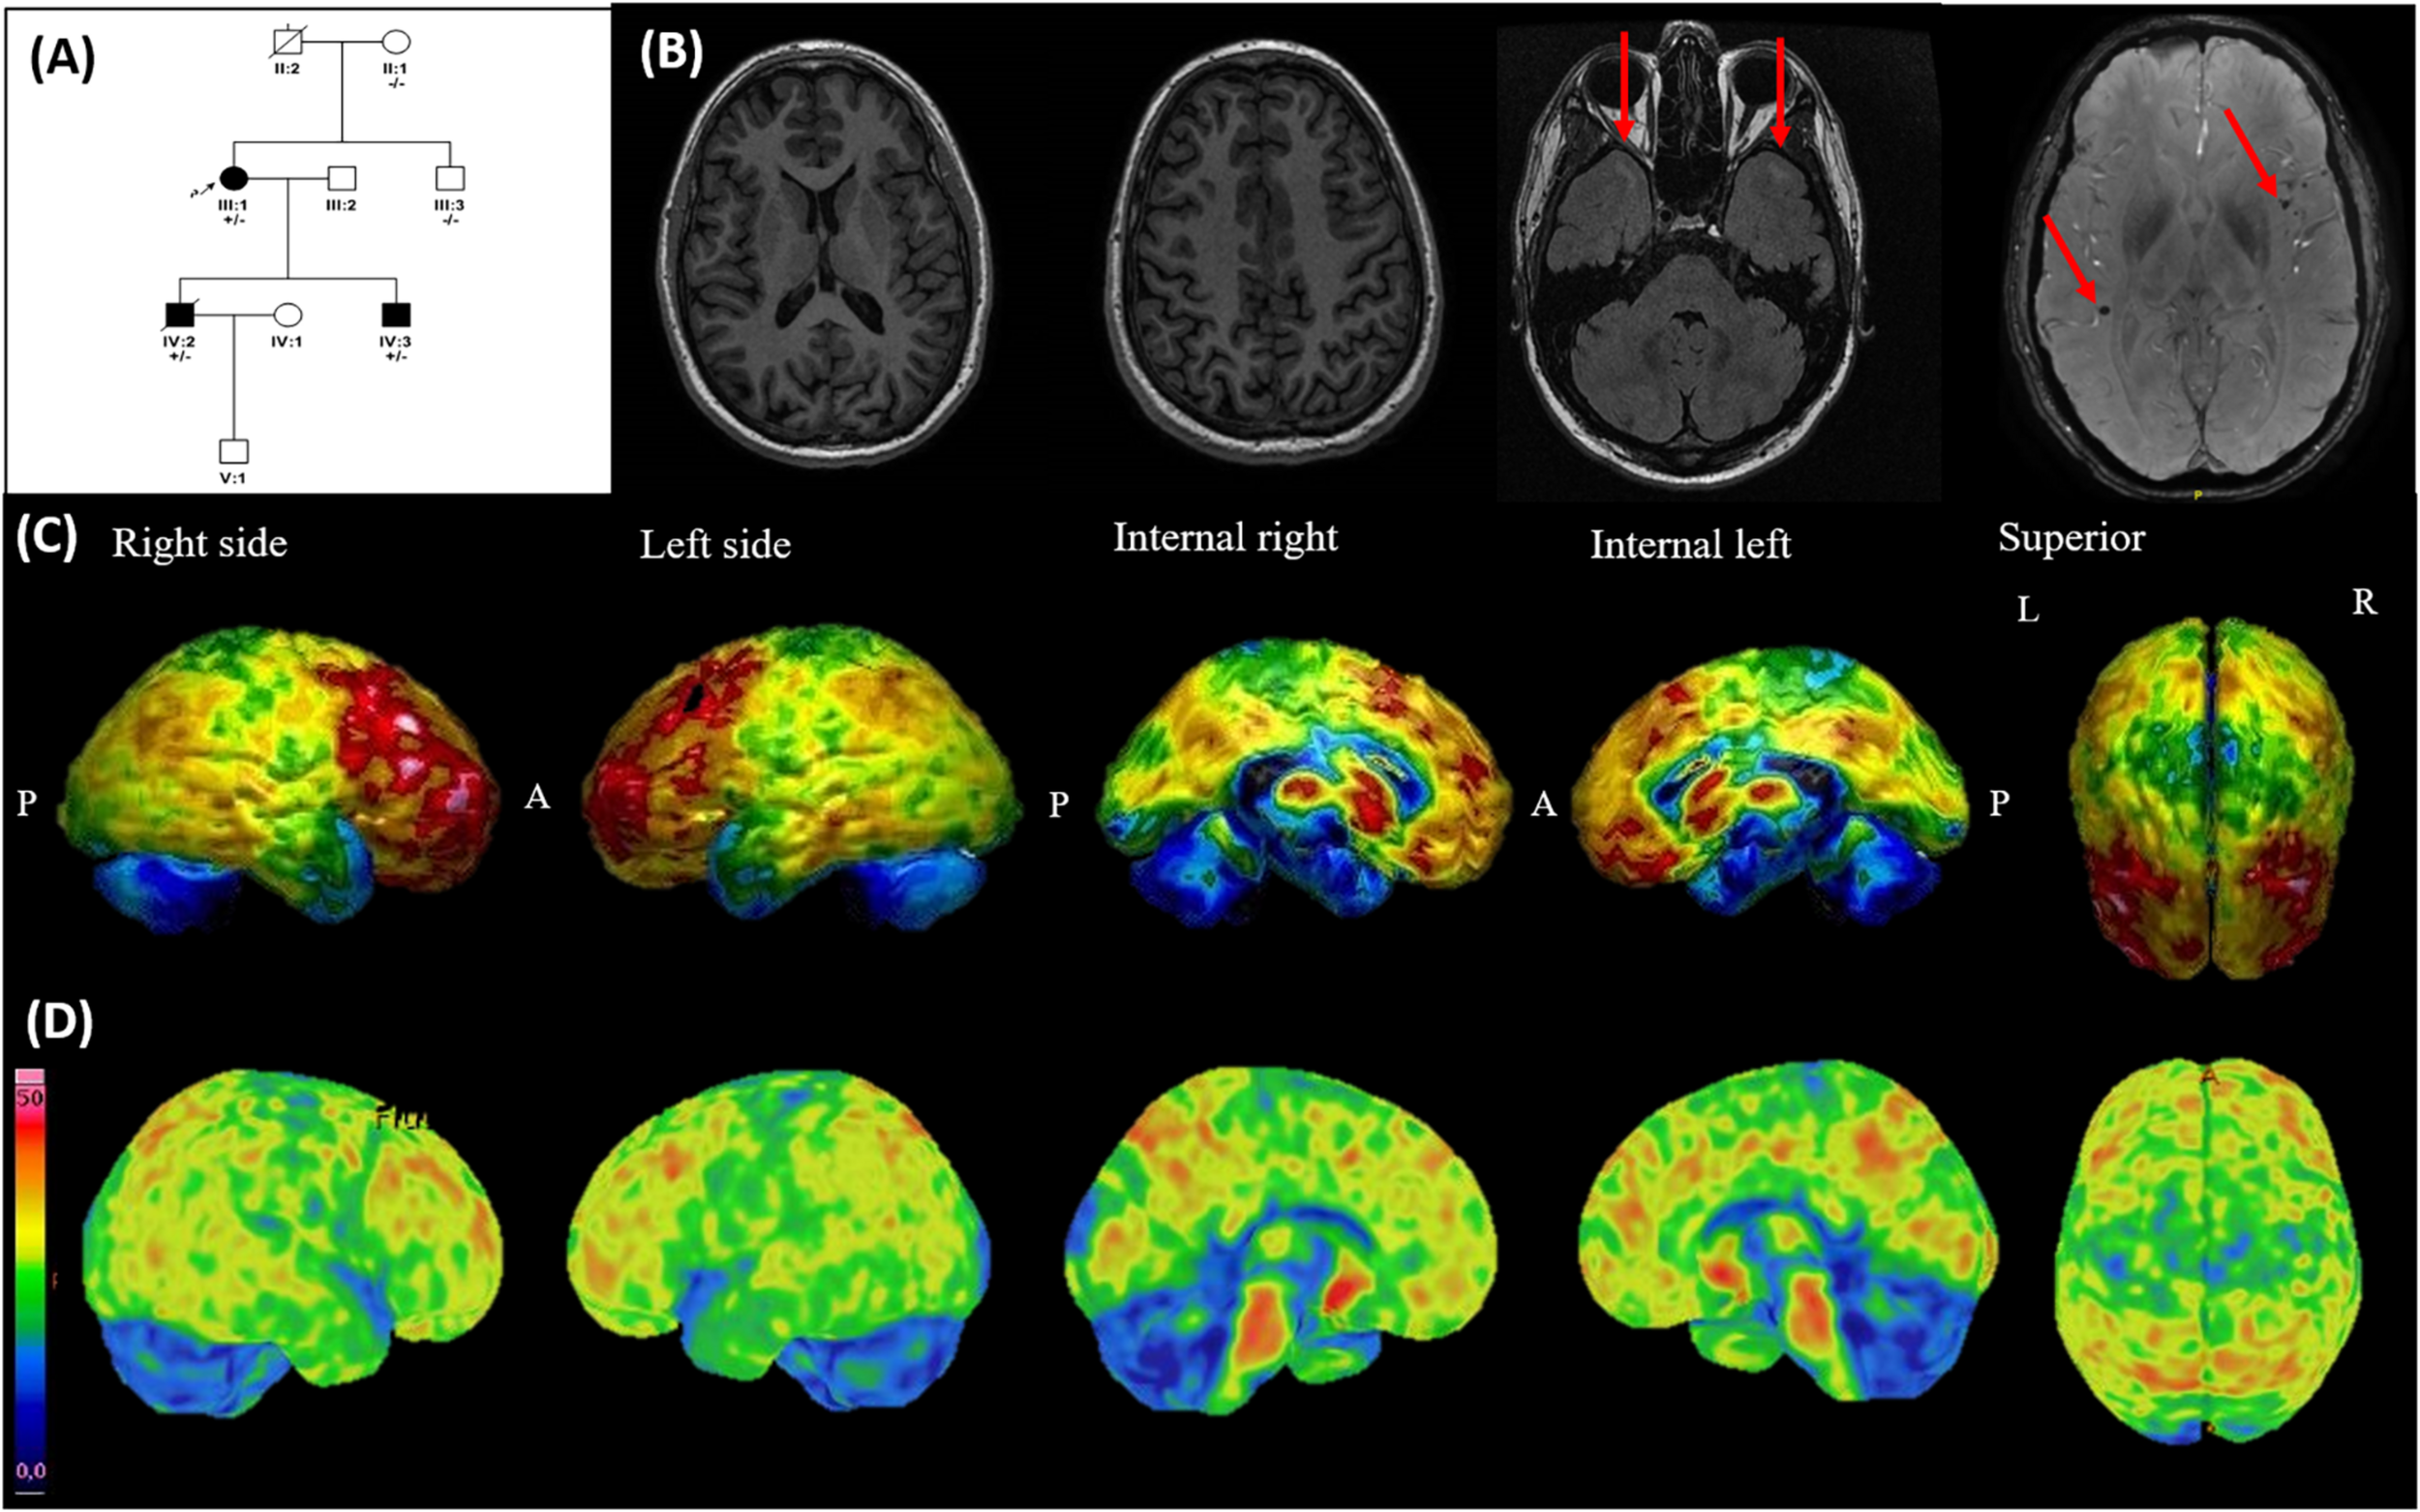

FIGURE 2

Family 2 pedigree, brain MRI, 18F-fludeoxyglucose PET (FDG-PET), and 18F-flutemetamol PET-TC. (A) Family pedigree: parents of the proband were unaffected, suggesting a de novo mutation. The arrow points to the proband. Dark symbols represent affected individuals. (B) Brain MRI of patient IV.2 at his 34 years old (6 years after disease onset). Left: two axial T1 images showing unspecific mild global cortical atrophy. Middle: axial FLAIR image, which reveals subcortical focal white-matter hyperintensities in the anterior temporal lobe (red arrows). Right: susceptibility-weighted (SW) image showing two microbleeds (red arrows). (C) FDG-PET of patient IV.3 shows bilateral hypometabolism in anterior temporal lobes, pre- and post-central gyri, and cerebellum. Colder colors represent lower glucose uptake. P, posterior; A, anterior; L, left; R, right. (D) 18F-flutemetamol PET of patient IV.3 shows diffusely increased amyloid binding in parietal and frontal lobes, sparing anterior temporal lobes, pre- and post-central gyri, and cerebellum. Colder colors represent lower amyloid binding.

In all three patients, routine blood tests and serologies were unremarkable, and neither clinical nor neurophysiological signs of LMN impairment were evident during the disease course. In both siblings, brain MRI showed mild unspecific cortical atrophy (Figure 2B). Scarcely scattered microbleeds together with focal white matter hyperintensities in the anterior temporal lobe were also visible in SWI and FLAIR, respectively (Figure 2B), but iron-related hypointensity in SWI along the motor cortex was absent. Brain FDG-PET of one sibling showed bilateral hypometabolism in anterior temporal lobes, pre- and post-central gyri, and cerebellum (Figure 2C).

Following this, the youngest sibling underwent an 18F-flutemetamol PET, which revealed diffuse increased amyloid binding in parietal and frontal lobes, but sparing the hypometabolic areas in the FDG-PET (Figure 2D).

More remarkably, in the patients harboring the p.Leu166Pro mutation, mild cognitive and behavioral symptoms appeared only several years after the motor symptoms onset and were masked by the motor symptoms. Although the father of proband could not be studied, the clinical and molecular information of the family (Figure 2A) suggests that a de novo mutation occurred in the proband. This is not surprising, since de novo mutations have been described in the same residue previously (Lyoo et al., 2016). Intriguingly, the FDG-PET in one of the patients showed hypometabolism in both anterior temporal lobes, pre- and post-central gyri, and cerebellum, a pattern neither suggestive of AD nor PLS (Van Laere et al., 2014). However, the disease progression toward akinetic mutism in the proband suggests that severe dementia might be a late feature in these patients. Moreover, the finding of microbleeds on brain MRI suggests the presence of amyloid angiopathy. Strikingly, the 18F-flutemetamol PET showed widespread amyloid deposition in the brain, except in the hypometabolic areas (Figure 2D), suggesting that amyloid was not responsible for the symptoms of patients. This is in agreement with a previous work, which suggested that Tau deposition in the primary motor cortex was responsible for the UMN signs in a patient harboring the same mutation (Lyoo et al., 2016). Moreover, previous studies suggest that non-amnestic symptoms are related to neurofibrillary tangles rather than to amyloid β plaques (Tang et al., 2016).